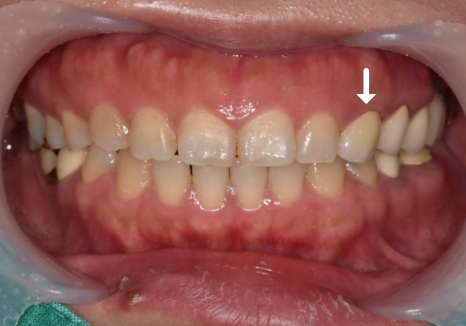

이러한 디테일한 과정을 거친 덕분에

옆 치아와 이질감 없이 밝고 자연스러운

색상으로 완성되었습니다. ^^

251101(전) 251108 (후)

다행히 이 환자분은 송곳니라

치아가 깨지기 전에

크라운 치료를 마칠 수 있었습니다.